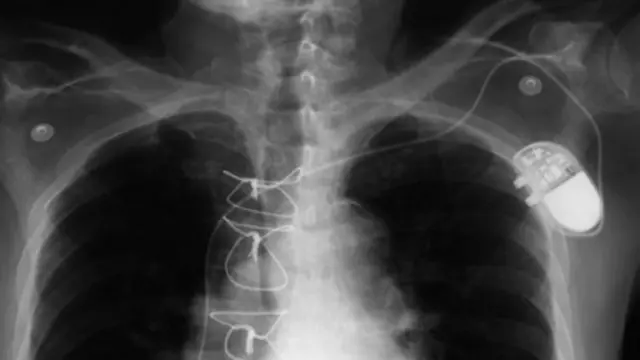

相比而言,起搏器和ICD往往必须在人去世后从体内取出——而且都要在火葬之前进行,因为里面的电池会在加热时爆炸。用于治疗疼痛的脊髓刺激器以及提供药物的内置泵同样如此,因为这些设备都内含电子元件。

一旦从体内移除,植入物往往都会废弃——欧盟、美国和其他一些地方都禁止重复使用植入式医疗设备。然而,在发展中国家重复使用这些设备却已经逐渐成为一种趋势。

一个起搏器卖4000美元,一个ICD卖2万美元,因此回收利用二手植入设备,是让很多人能够买得起这种救命产品的唯一方式。在英国,慈善组织Pace4Life从殡仪馆回收仍然能够继续使用的起搏器供印度人使用。类似地,《内科医学年鉴》最近发布了一个名为“My heart Your Heart”的项目得出的研究结论:他们发现,使用二手ICD的75名病人并没有出现感染或故障等问题。该项目目前正在向美国食品和药品管理局(FDA)申请,希望能将回收而来的心脏设备销售到海外。